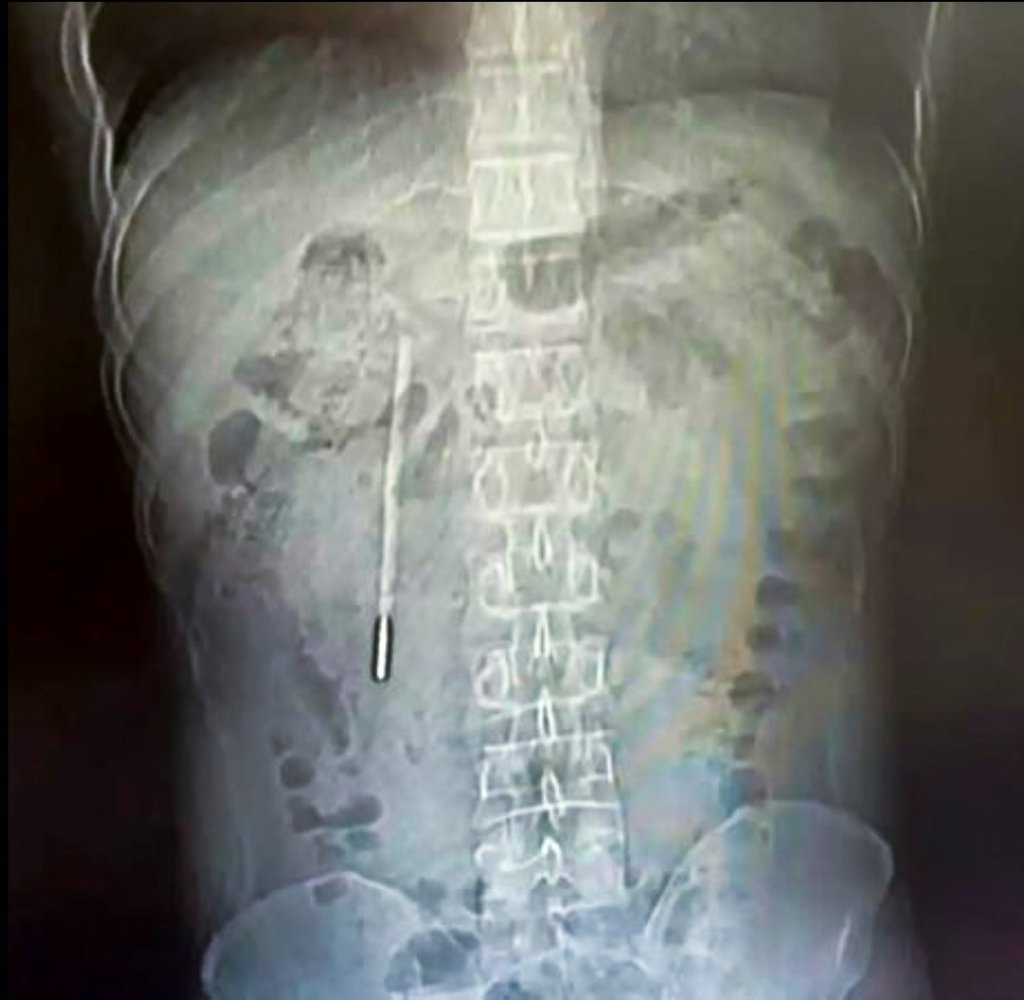

Theo kết quả từ các biện pháp chẩn đoán hình ảnh và chụp chiếu, các bác sĩ chuyên khoa đã phát hiện một dị vật nằm sâu bên trong tá tràng của bệnh nhân. Căn cứ vào hình dáng và đặc điểm trên phim chụp, đội ngũ y tế đã đặt ra nghi ngờ rất lớn rằng vật thể lạ này chính là một chiếc nhiệt kế thủy ngân.

Tình trạng lúc bấy giờ được đánh giá là vô cùng nguy hiểm. Phần đầu nhọn của chiếc nhiệt kế đang trong trạng thái ép trực tiếp vào lớp thành ruột của bệnh nhân. Vị trí và tư thế này đặt ra một nguy cơ cực kỳ cao về việc gây thủng ruột và dẫn đến tình trạng chảy máu trong nghiêm trọng, đe dọa trực tiếp đến tính mạng của người bệnh nếu không được can thiệp kịp thời.

Rất may mắn, thiết bị được lấy ra vẫn còn giữ được hình dạng nguyên vẹn ban đầu, mặc dù các vạch đo nhiệt độ in trên thân nhiệt kế đã bị mờ nhạt đi theo thời gian do tác động của môi trường dịch vị.